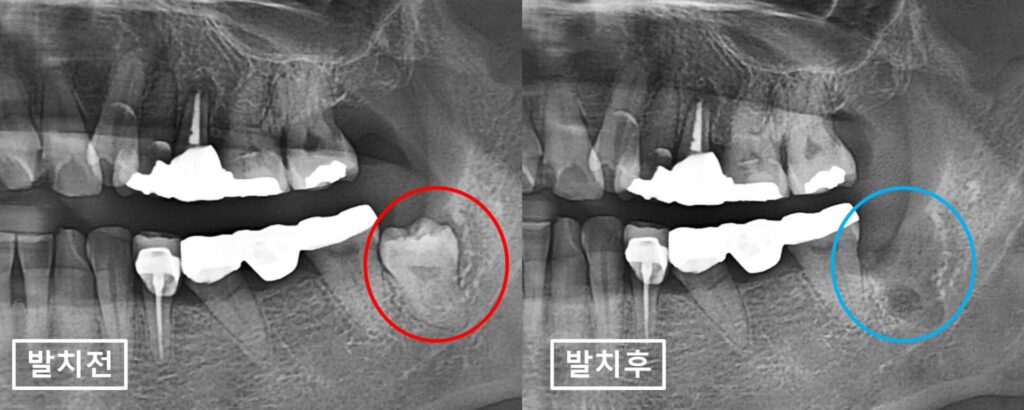

24.03.09(초진) / 24.03.11(치료 후) – 57y 박OO님

환자분께는 의뢰주신 선생님,

그리고 저역시도

현재 나타난 원인모를 치통이

매복사랑니의 염증에 의한 것인 것 같고

매복사랑니를 발치하고 증상이 어떤지

지켜보자고 말씀드렸습니다.

다행히

발치 후 치통은 사라졌고

위에서 설명드린 매복사랑니 발치 후

정말 간혹 나타날 수 있는

설신경 손상 역시 없었습니다.

다행이네요.